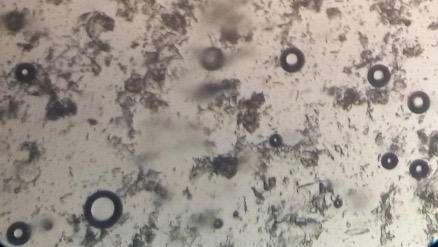

Preparation of niosomes from proniosomes and morphological evaluation (Photomicroscopy)

The optical photographs of all reconstituted proniosomal formulae are shown in fig. (1-28). The photographs revealed that the formed niosomes are unilamellar vesicles with a spherical shape and smooth surface. The vesicles were insular and separate without aggregation or lumping. Apparently, proniosomal formulae containing span 40 and span 60 yielded vesicles of large numbers with well-identified outline and core which will affect the entrapment efficiency of loaded drug directly. However proniosomal formulae containing span 20 and span 80 produced small numbers of vesicles with a slightly different outline. This may be due to the high phase transition temperatures of both span 40 and span 60 which will cause the formation of a large number of stable niosomal vesicles. The phase transition temperatures for span 20, 40 and 60 are 16, 42 and 53 °C; respectively, however, span 80 possess the lowest phase transition temperature at 12 °C [35]. This explains why proniosomal formulae containing span 20 and span 80 produce small numbers of vesicles upon hydration.